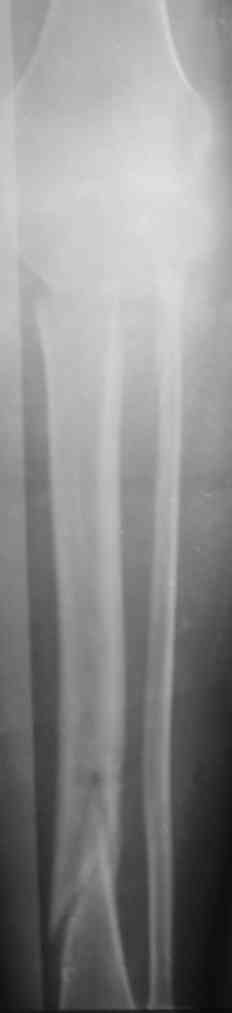

Патологический перелом голени, остеомиелит |

Уважаемые коллеги!Женщина 30 лет,инвалид 1-й группы по рассеяному энцефаломиелиту (клинически нижний парапарез). В январе 2008 года получила закрытый винтообразный перелом большеберцовой кости в н/з и шейки малоберцовой кости со смещением отломков. После травмы развились обширные эпидермальные пузыри голени и голеностопного сустава. После заживления ран произведено наложение аппарата Илизарова. П/о период без особенностей, больная поставлена на ноги (с ходьбой, естественно, проблемы). Наблюдалась на дому. Спустя месяц после операции отмечалось воспаление м/тканей области спиц проксимального базового кольца аппарата, отек в/з голени (больная передвигалась по дому на четвереньках!).Пришлось поменять кольцо на больший диаметр.Воспаление купировали. К концу второго месяца фиксации воспаление в области верхних спиц опять возникло, отделяемое сукровично-гнойное, незначительное. Проводилось местное лечение, отмечался умеренный отек голени в в/з, болезненность, гиперемии не было. Через три месяца после операции - клиническая проба, перелом сросся. Аппарат демонтирован. Спустя 4-5 дней после демонтажа отмечалась гипертермия до 39 в вечернее время. Раны кроме верхних зажили без проблем, верхние - в прежнем состоянии (незначительное серозное отделяемое).Проводилась АБТ, туалет ран, дренирование. Спустя 2 недели после снятия аппарата мать больной отметила появление подвижности в области коленного сустава. При осмотре - деформация голени в в/з (на уровне верхних спиц), подвижность на протяжении в/з, болезненность. Отек умеренный в в/з, гиперемии нет, гипертермия локальная умеренная.Коленный сустав отечен, жидкости нет. Сделали снимки (в приложении) - вот какая картина Больную госпитализировали - гипсовая лонгета, противовоспалительная терапия, взяли посев из ран. В анализах -лейкоциты до 8 тыс, сдвига формулы нет, СОЭ 42, но больная проходит курсы лечения бетафероном по РЭМ. Ваши мнения по поводу данной больной. С уважением А. В. Л.